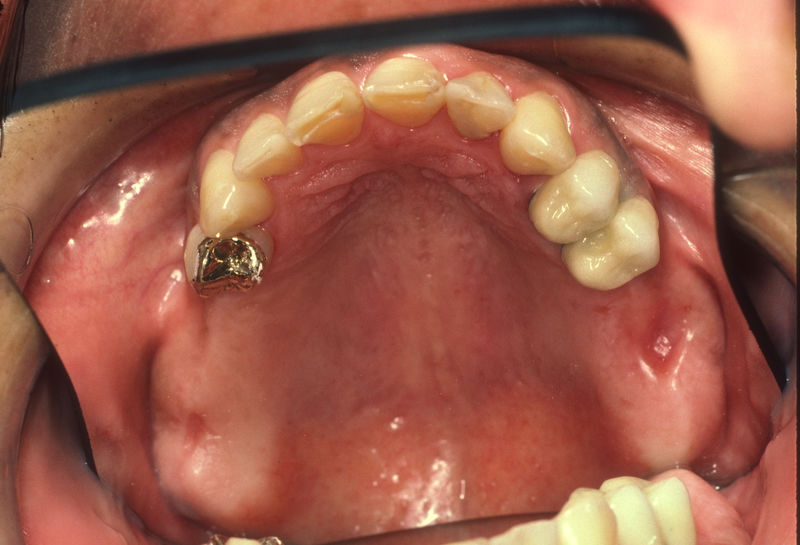

Implante fracasado, extracción, carillas, coronas y prótesis fija.